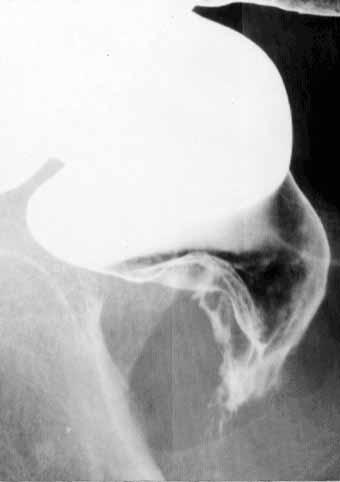

直腸部から肛門の類基底細胞癌のX線像  直腸の病変部をX線像で二重造影像にて描出した写真です。病変は、ほぼ側面に近い像として描出されています。主に後壁にあって、直腸下部から肛門管部にかけて陰影欠損を呈し、その中央部には、不整形の潰瘍を形成しています。病変の口側はなだらかな立ち上がりを示し、隆起の表面は平滑な線で構成され、粘膜下腫瘍様の所見を示しています。

疾患(病理主体)の分類悪性上皮性腫瘍/類基底細胞癌

腫瘍の肉眼分類2型(潰瘍限局型)/

病変の最大径(ミリ)40以上

腫瘍の深達度ss(a1)